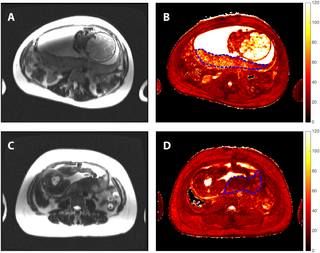

For post-op monitoring of patients who had pancreatic ductal adenocarcinoma (PDAC) resection, a new study showed that diffusion-weighted magnetic resonance imaging (MRI) had enhanced sensitivity for detecting recurrent tumors in comparison to conventional MRI.